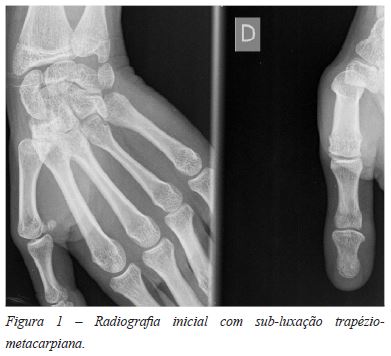

Uma criança de 12 anos, de sexo feminino, caucasiana e sem antecedentes de relevo foi encaminhada para consulta de Ortopedia por dor e sensação de instabilidade na região da articulação trapeziometacarpiana da mão direita, com cerca de um na de evolução e agravamento progressivo. A doente negava traumatismo agudo, referindo tocar violoncelo várias horas por dia, desde os sete anos de idade, atividade para a qual apresentava limitação crescente desde o inicio das queixas. O estudo inicial com radiografia em dois planos revelou sub-luxação da articulação trapeziometacarpiana (Figura 1), tendo sido inicialmente instituído tratamento funcional, com realização de fisioterapia durante 3 meses. Por persistência das queixas, optou-se por redução fechada da articulação e imobilização com aparelho gessado durante 5 semanas, mas a ausência de melhoria clinica ou radiológica levou ao avanço para tratamento cirúrgico.